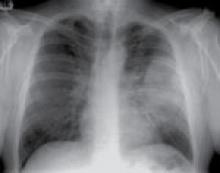

When should you admit a patient with suspected CAP?

When the patient has 2 or more of the following CURB-65 criteria: respiratory rate ≥30, acute confusion, low blood pressure (systolic blood pressure <90 or diastolic BP ≤60 mm Hg), blood urea nitrogen [BUN] >19.6 mg/dL, and age ≥65 years (strength of recommendation [SOR]: B, based on 3 prospective cohort studies). Alternatively, consider hospitalization for patients presenting with a Pneumonia Severity Index (PSI) class of 4 or 5 (SOR: B; 1 prospective cohort study). There are no studies that test whether using these rules improve outcomes over standard care.